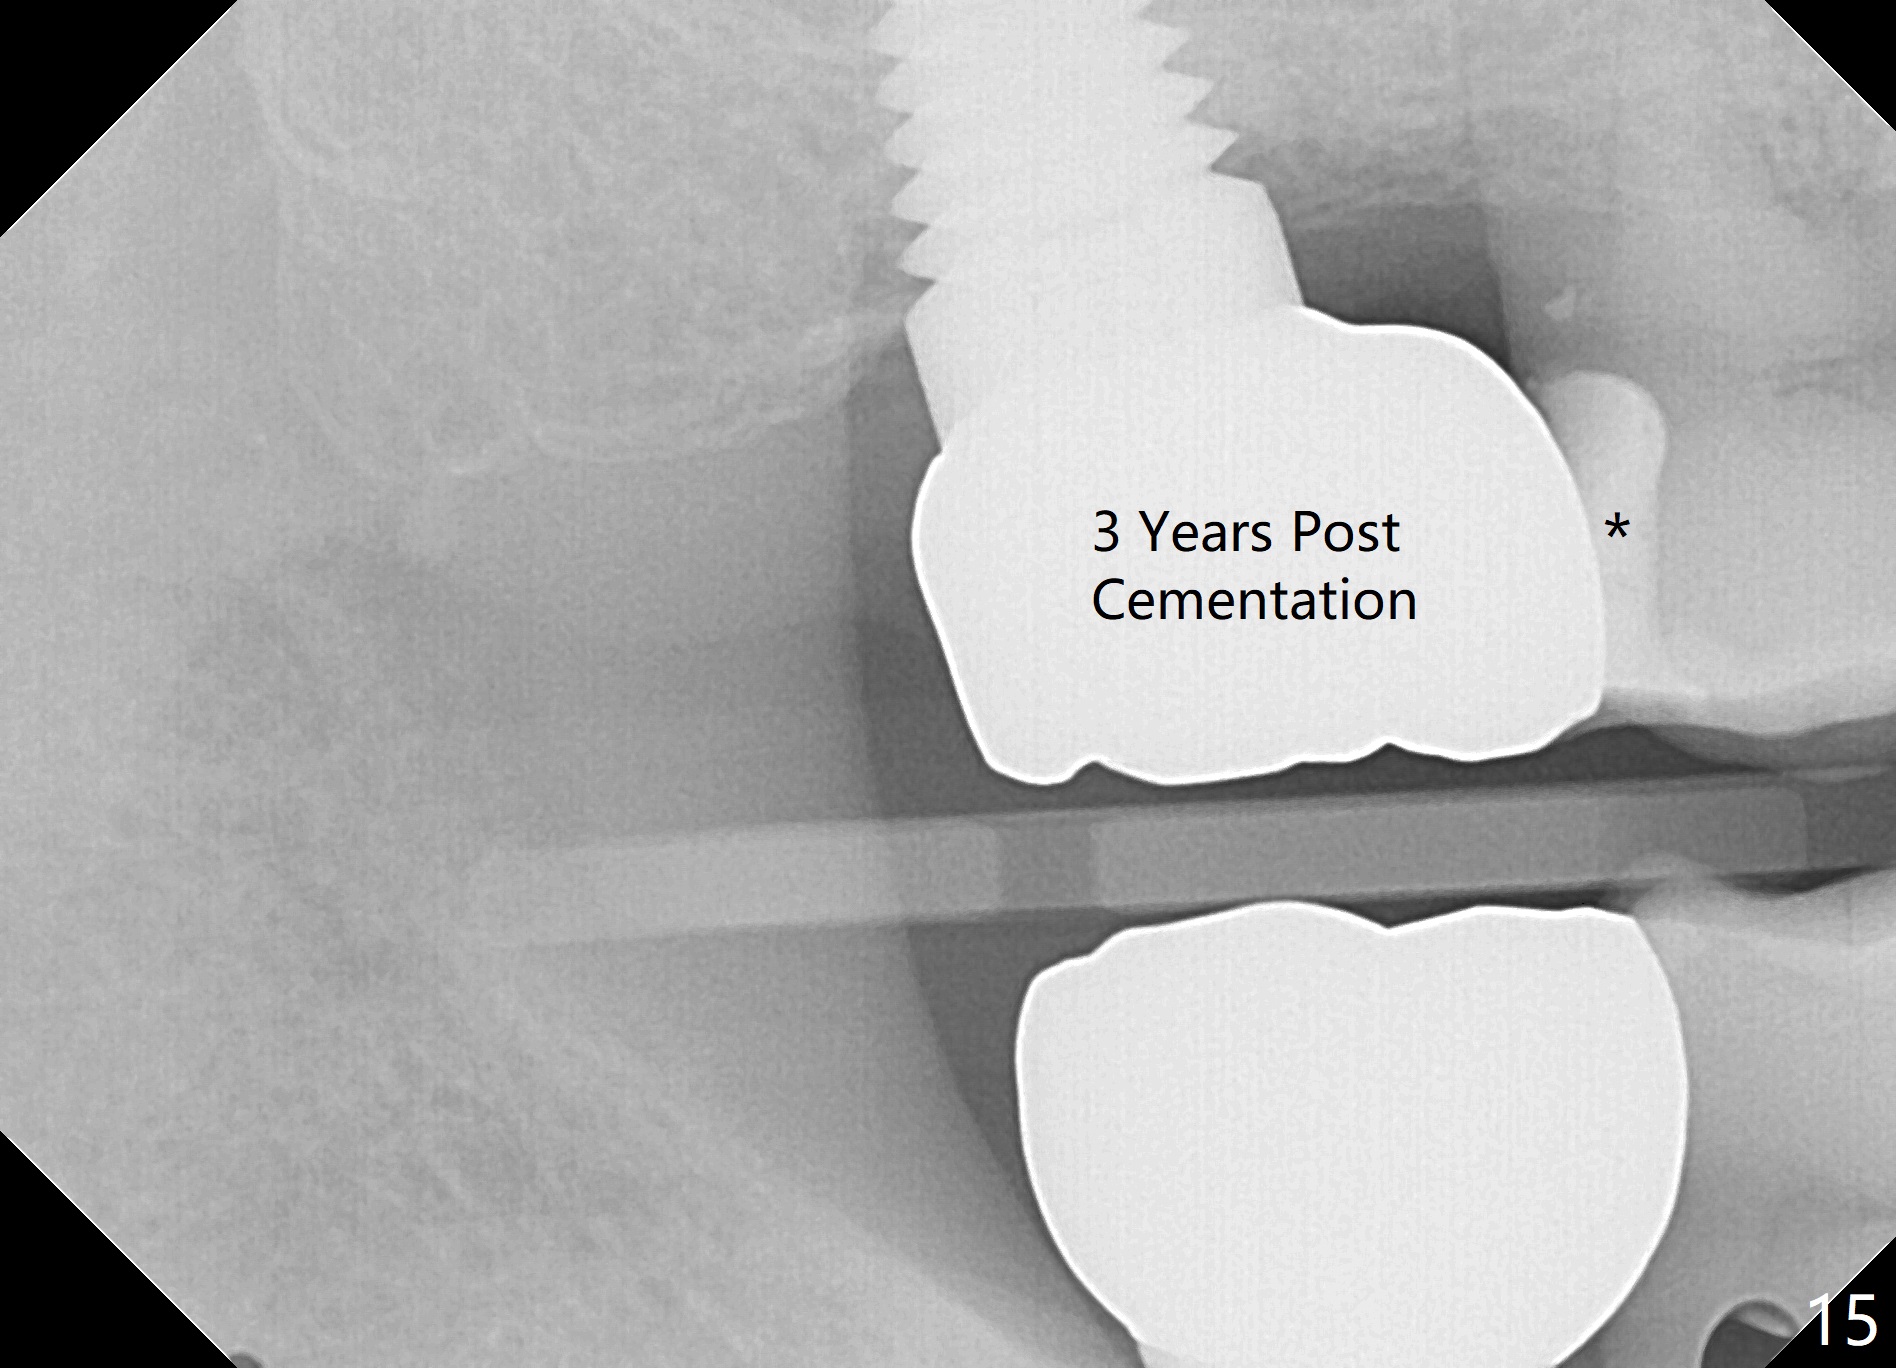

The patient returns for final restoration 22 months postop (Fig.12). Implant threads are embedded in the bone. Panoramic X-ray is taken after removal of perforated provisional and abutment. The implant remains asymptomatic 1 year post cementation (Fig.13) in spite of the fact that there appears to be no palatal plate (Fig.14 (1.5 years post cementation)). It is probably related to the thick palatal (P) gingiva. Periimplantitis develops 3 years post cementation and immediately post #15 implant 2nd removal. The implant is found to be palatal when #3 DO composite is placed (Fig.15). Oral hygiene appears to be difficult to maintain in spite of use of water pik. His diabetes is under control with Insulin.